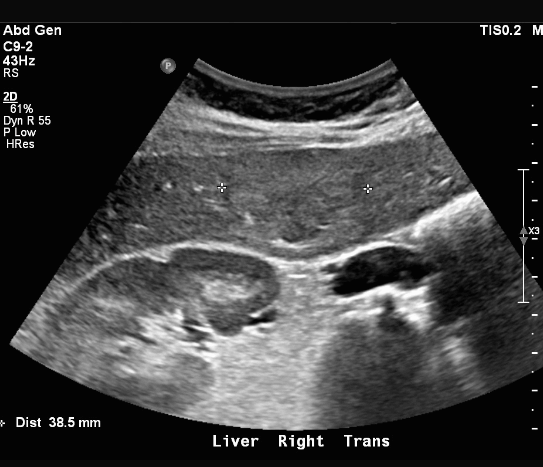

hepatocellular adenoma (간세포선종) US finding

- 원형의 저에코, 등에코, 고에코등의 종괴로 다양하다.

- 피막을 갖는다

- 크기가 8~14cm으로 크다

- 간전이암이나 간세포암과 정확히 구별이 어렵다.

- hypoechoic rim (띠가 혈관이다)

- usually solitary and heterogeneous